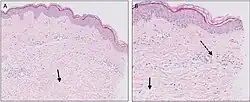

The skin lesions of urticarial disease are caused by an inflammatory reaction in the skin, causing leakage of capillaries in the dermis, and resulting in an edema which persists until the interstitial fluid is absorbed into the surrounding cells.